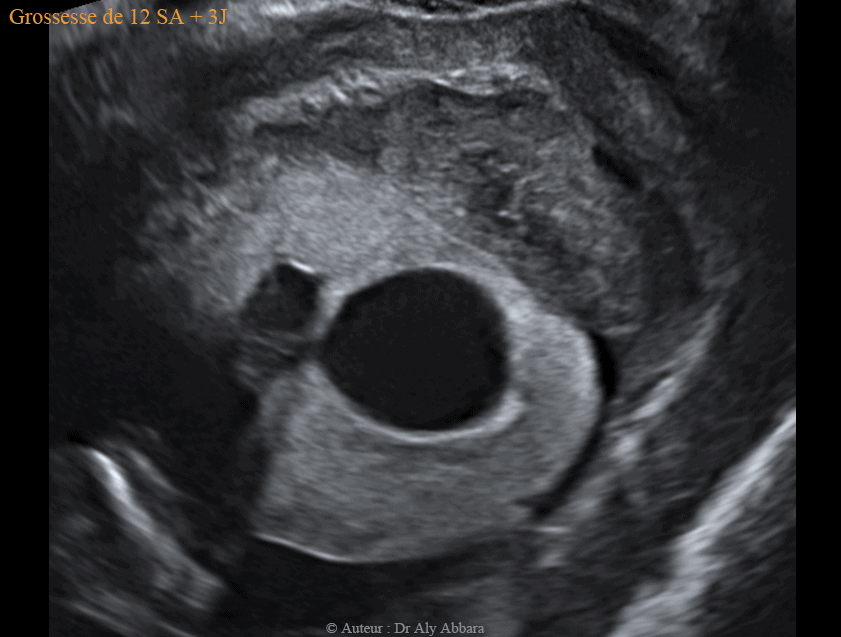

Kyste placentaire cytotrophoblastique intra-parenchymateux associé à la présence d'un hématome rétroplacentaire - grossesse de 12 SA et 3 J

Dans le cas présenté dans cet article, le kyste placentaire intra-parenchymateux, cytotrophoblastique, prend la forme d'une formation intra-placentaire, unique, uniloculaire, à contenu anéchogène et à paroi hyper-échogène, mais sans végétations endophytiques et sans zone d'épaississement.

Ce kyste évolue dans le parenchyme placentaire, mais au niveau d'un de ses deux pôles, il atteint la face fœtale du placenta à un point correspondant à la zone de l'insertion du cordon ombilical.

Le kyste mesure 26 x 21 x 23 mm de diamètre (6,4 cm3 de volume).

Il a été mis en évidence à 12 SA et 3 jours ; il est en association avec un décollement partiel du placenta aboutissant à la formation d'un hématome rétro-placentaire (et rétro-cervical utérin) de 42 x 21 x 52 mm de diamètre (soit 24 cm3 de volume).

Cet HRP se manifeste cliniquement par des métrorragies modérées depuis plusieurs semaines, mais la grossesse évolue normalement : foetus vivant et morphologiquement normal, avec longueur crânio-caudale "LCC" = 61,75 mm, et clarté nucale = 1,51 mm.